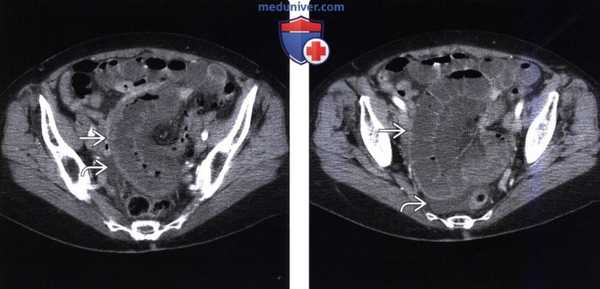

(б) При ангиографии выявлена аневризма в проксимальном отделе ВБА (стрелка), был установлен стент. ПШГ у мальчика 11 лет. При контрастно-усиленной КТ в аксиальной проекции выявлены утолщение стенок тонкой кишки (указатели), тяжистое уплотнение брыжеечной жировой клетчатки и асцит. ШГ у мальчика 10 лет.

(а) При контрастно-усиленной КТ в аксиальной проекции выявлено сегментарное утолщение стенок тонкой кишки (стрелки).

(б) При рентгенографии тонкой кишки с пассажем бария отмечено сегментарное утолщение складок тонкой кишки (указатели). Волчаночный энтерит. При КТ с контрастированием в аксиальной проекции выявлены сегментарное утолщение стенок тонкой кишки и симптом «мишени» (стрелки).

Внутренний накапливающий контраст слой, средний гиподенсивный слой и наружный накапливающий контраст слой представляют собой гиперемированную слизистую оболочку, отечный подслизистый слой и гиперемированные мышечный и серозный слои, соответственно. Отмечено также тяжистое уплотнение жировой клетчатки (указатели). Волчаночный энтерит. При КТ с контрастированием в коронарной проекции выявлены сегментарное отечное утолщение петли тонкой кишки (стрелки) и застой в брыжеечный сосудах, проявляющийся симптомом «гребня» (указатели). Болезнь Бехчета у мужчины 54 лет.

(а) КТ с контрастированием, аксиальная проекция: сегментарное утолщение стенок терминального отдела подвздошной кишки и накопление в них контраста (указатели).

(б) КТ с контрастированием, коронарная проекция: утолщенные и накапливающие контраст стенки слепой кишки и терминального отдела подвздошной кишки (стрелки).

(в) При рентгенографии с применением бария отмечены множественные дефекты наполнения в терминальном отделе подвздошной кишки, обусловленные изъязвлениями (короткие стрелки), и разрушение илеоцекального клапана (длинная стрелка). Болезнь Бехчета у женщины 37 лет.

(а) КТ с контрастированием, аксиальная проекция: массивное утолщение стенки кишки в области илеоцекального клапана (стрелка).

(б) При рентгенографии с контрастированием выявлены массивный дефект наполнения с центральной язвой в области слепой кишки (длинная стрелка), изъязвления и утолщение стенки терминального отдела подвздошной кишки, а также разрушение илеоцекального клапана. Синдром Чарга-Стросса (васкулит мелких сосудов), проявляющийся болью в животе и лейкоцитозом.

(а) При контрастно-усиленной КТ в коронарной проекции визуализированы сегментарное утолщение стенки тонкой кишки с накоплением в ней контраста и тяжистое уплотнение брыжеечного жира (указатели). Также выявлен пневмоперитонеум (стрелки), что предполагает наличие перфорации кишки.

(б) На резецированном участке тонкой кишки обнаружены множественные изъязвления, эрозии и перфорация. При микроскопии образца установлен некротизирующий и гранулематозный васкулит с эозинофильной инфильтрацией, что соответствует синдрому Чарга-Стросса.